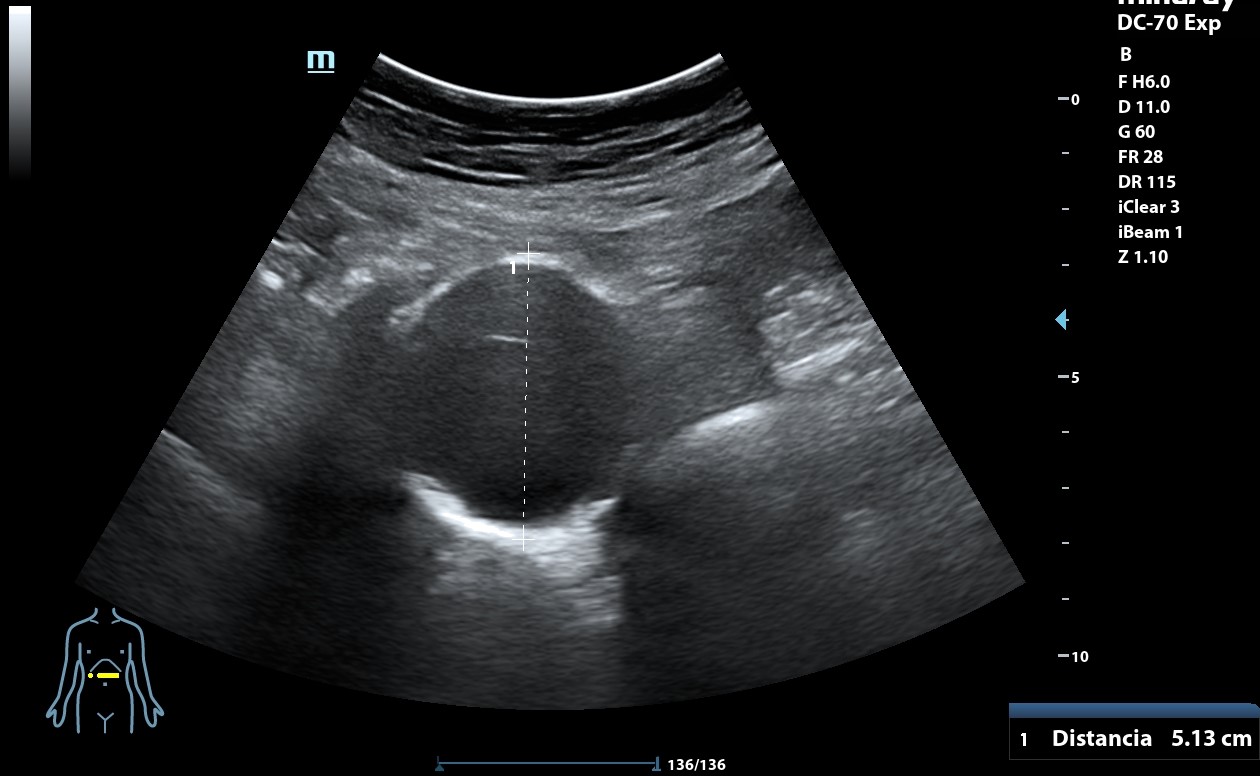

Ecografía clínica: arteria femoral dilatada con material hipoecoico heterogéneo en su pared lateral con un diámetro de 5,85 x 5,88 cm. Dilatación de aorta infrarrenal de 5,1 cm.

Diagnóstico: Aneurisma de arteria femoral derecha. aneurisma de aorta.